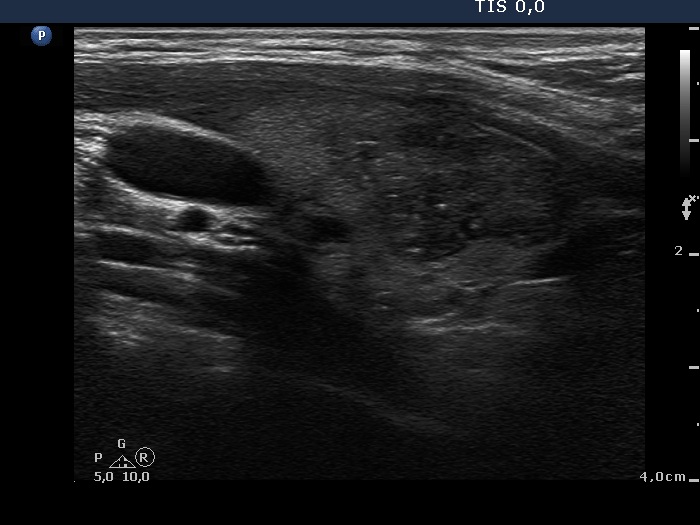

Intranodular hyperechogenic figures - case 951 (ultrasonographic picture 8)

Lower part of the right lobe, another longitudinal scan.